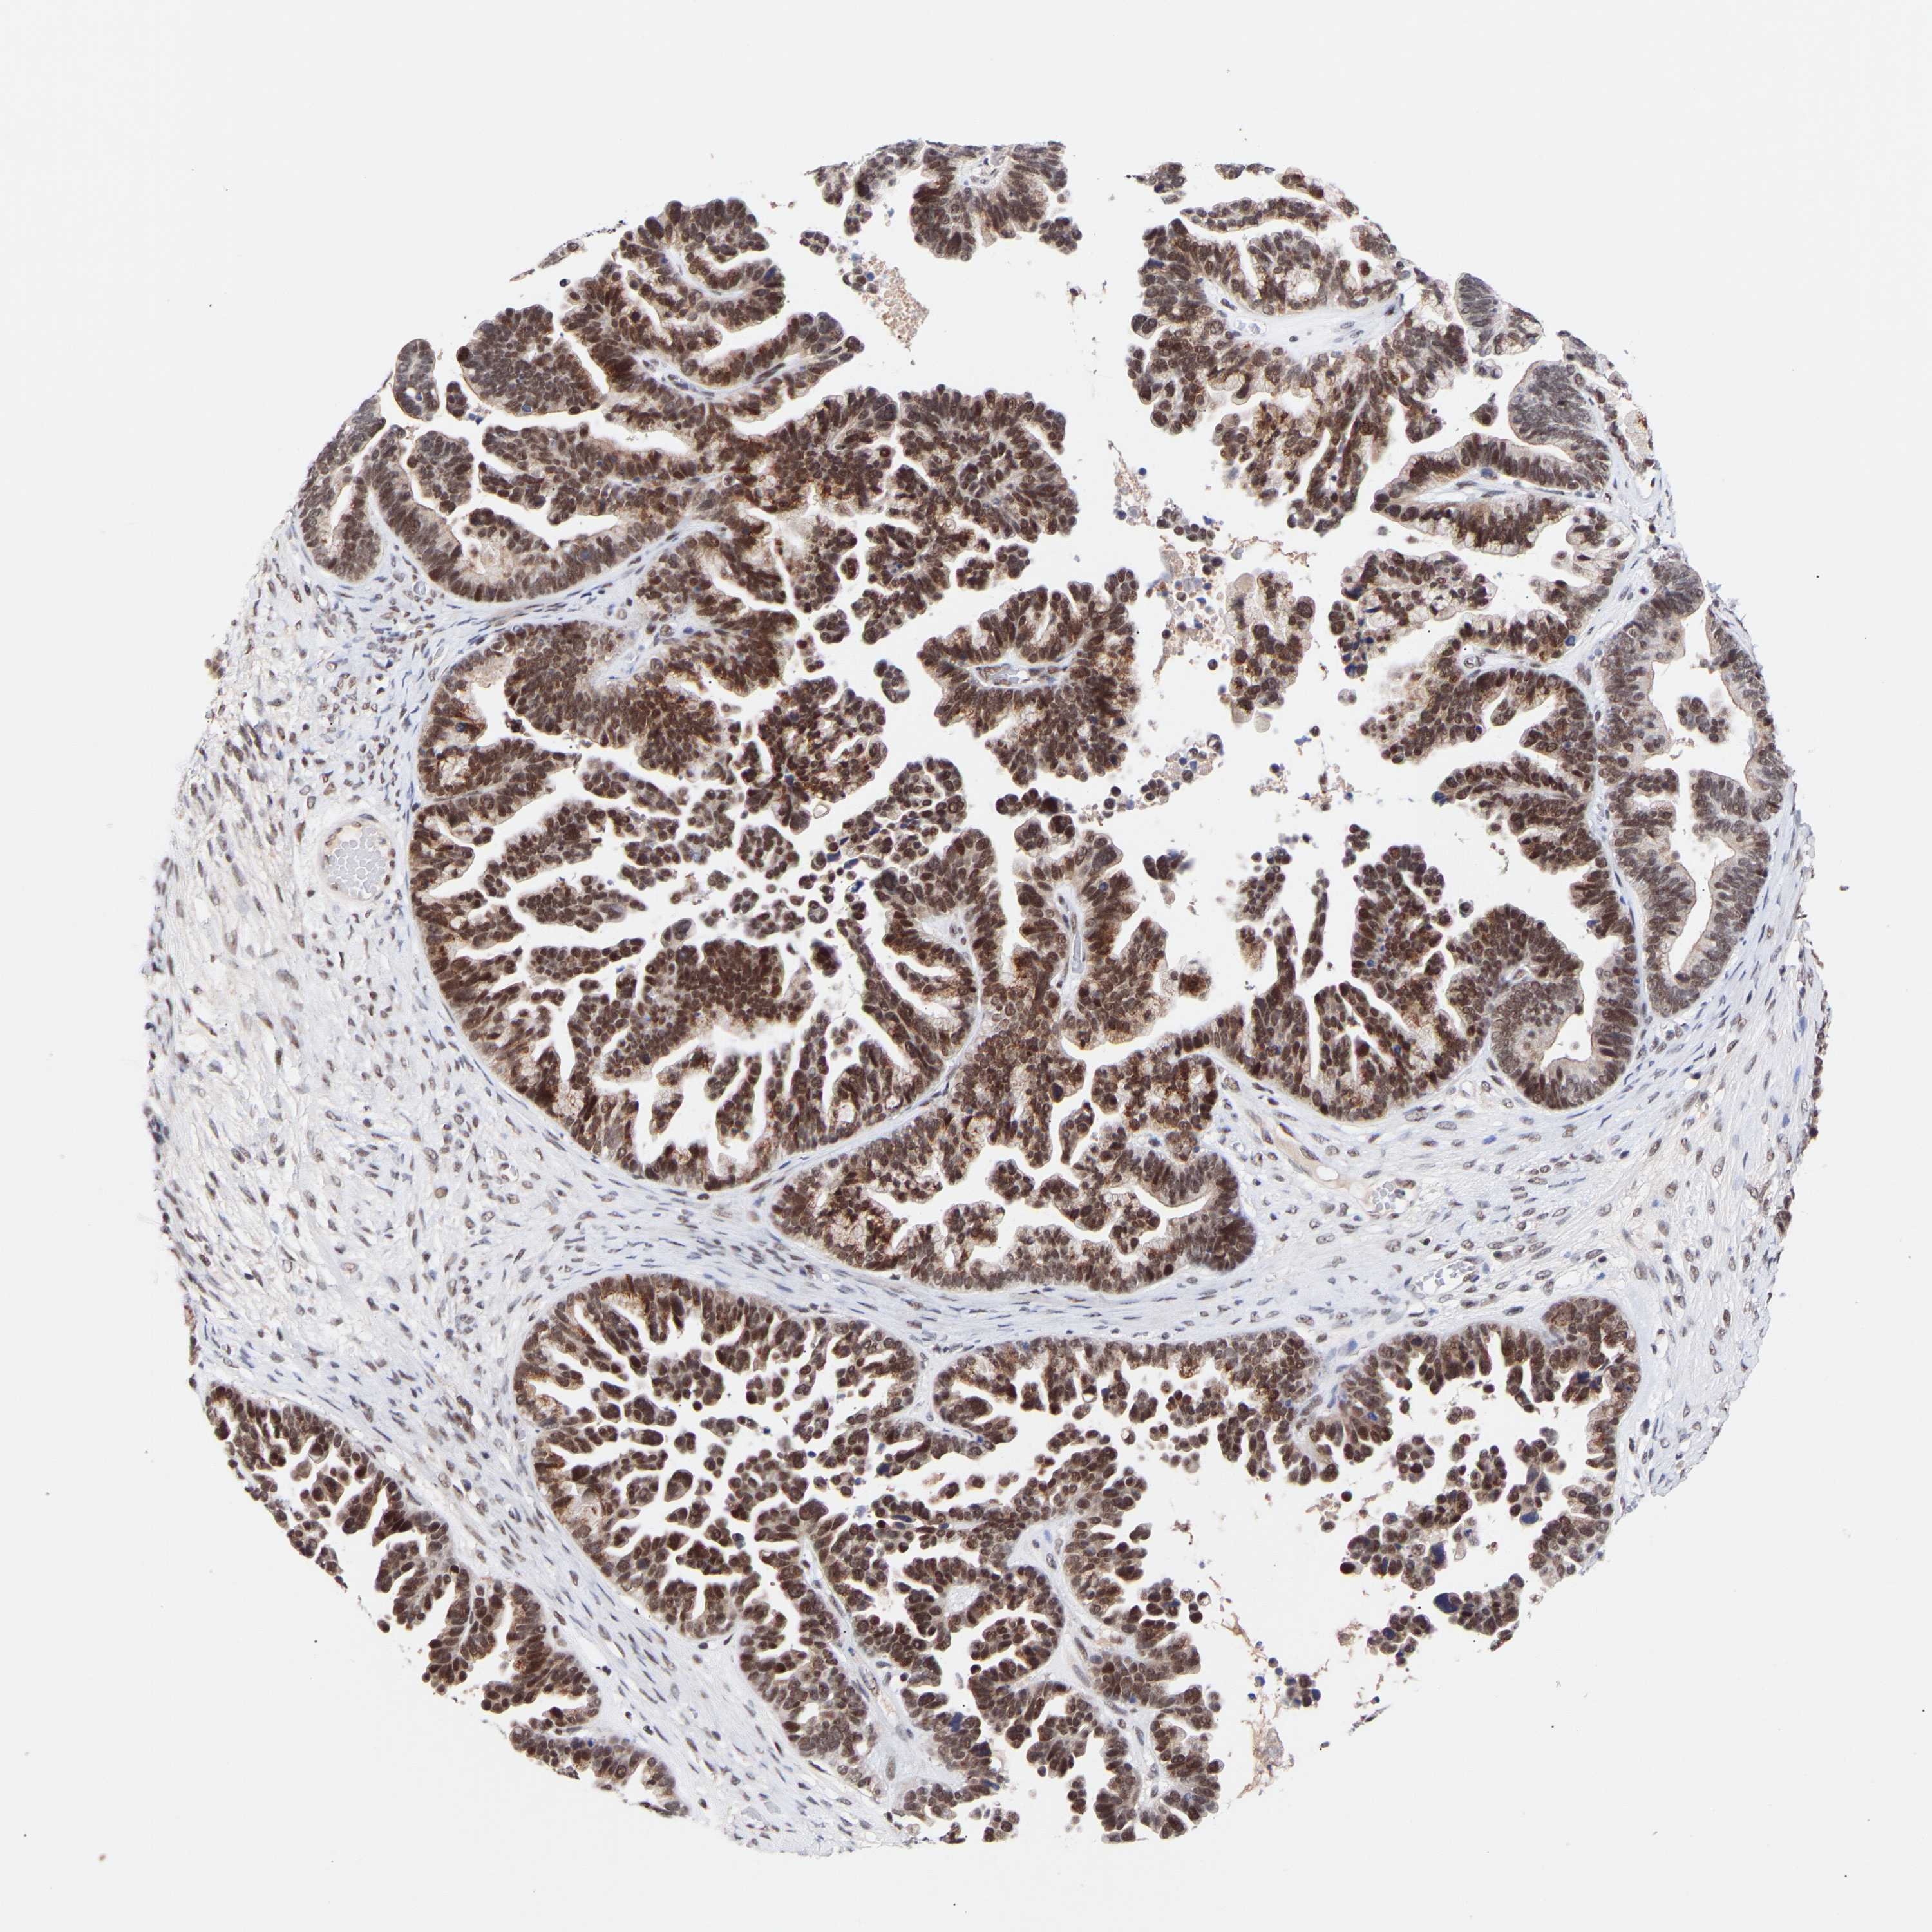

OVARIAN CANCER - Protein expressioni

A mouse-over function shows sample information and annotation data. Click on an image to view it in a full screen mode. Samples can be filtered based on level of antibody staining by selecting one or several of the following categories: high, medium, low and not detected. The assay and annotation is described here.

Note that samples used for immunohistochemistry by the Human Protein Atlas do not correspond to samples in the TCGA dataset.

Antibody stainingi

Antibody staining in the annotated cell types in the current human tissue is reported as not detected, low, medium, or high, based on conventional immunohistochemistry profiling in selected tissues. This score is based on the combination of the staining intensity and fraction of stained cells.

Each image is clickable and will lead to virtual microscopy that enables deeper exploration of all samples and also displays staining intensity scores, fraction scores and subcellular localization as well as patient and tissue information for each sample.

Antibody HPA019824

Antibody CAB015201

Cystadenocarcinoma, serous, NOS

Carcinoma, endometroid

Cystadenocarcinoma, mucinous, NOS

Carcinoma, NOS